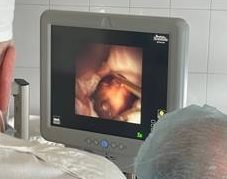

В этом году врачи-урологи Ульяновского областного клинического центра специализированных видов медицинской помощи провели три успешные операции, применив новый метод, – интраренальную хирургию.

«На сегодняшний день ретроградная интраренальная хирургия является самым современным и эффективным методом хирургического лечения мочекаменной болезни, в том числе и в сложных случаях. Во время операции может использоваться как спинномозговая анестезия, так и общий наркоз. Главная задача – сохранить возможность управлять дыхательными процессами пациента и обеспечить при этом полное расслабление и отсутствие боли. Доступ к камню осуществляется через естественные мочевые пути: во время операции происходит минимальная травматизация мочевыделительных путей, что способствует скорейшему выздоровлению и максимально снижает риск послеоперационных осложнений», – рассказывает заведующий урологическим отделением УОКЦСВМП Александр Шмырин.

По словам специалистов, при интраренальной хирургической процедуре эндоскоп малого диаметра с лазером заводится в специальном кожухе, который защищает мочеточник и уретру, в мочевыделительные пути, чашечно-лоханочную систему почки после предварительного стентирования мочеточника.

«Безопасность процедуры, полное отсутствие кровопотери, минимальное воздействие на мочеточник и мягкие ткани благодаря применению гибкого инструмента, повторяющего все анатомические изгибы мочеточника при доведении его до почки, сочетаются с высокой эффективностью операции: режим лазерного дробления разрушает камни на мельчайшие частицы», - отмечают в пресс-службе министерства здравоохранения Ульяновской области.

Фото: минздрав